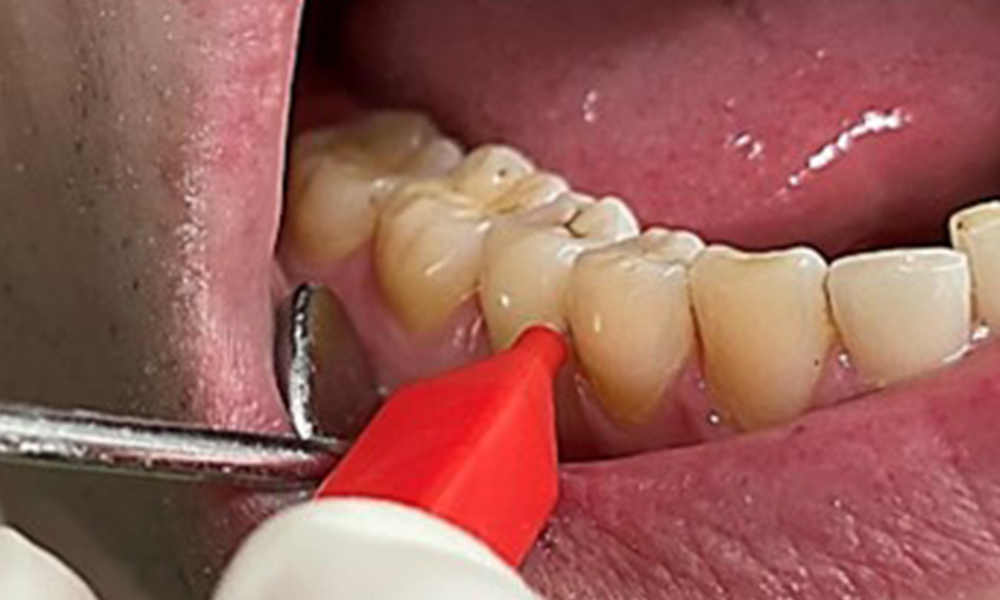

Die Raucher- und Teeverfärbungen lassen sich mittels Pulverstrahl gut entfernen (Abb. 11).

Bei Verwendung des höher abrasiven Pulvers ist dringend darauf zu achten von zervikal nach koronal zu arbeiten und die Auslassdüse niemals Richtung Gingiva zeigen zu lassen, um eine mögliche Emphysembildung zu vermeiden. Eine gegenüberliegende gute Absaugung ist unabdingbar zur Reduktion des Aerosols (Abb. 12).